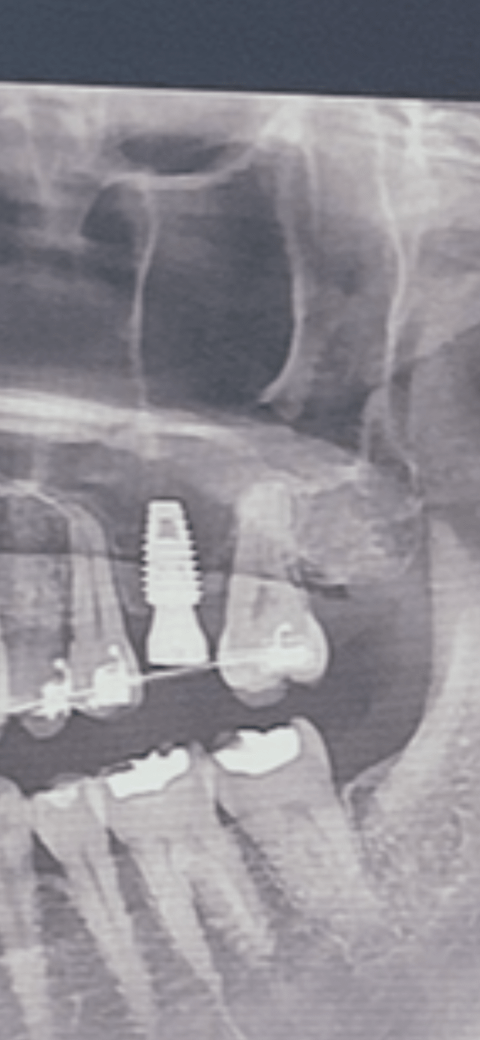

임플란트는 기존치아와 달리 뼈와 osseointegration으로 결합되어 있는 구조입니다. 즉 만약 임플란트가 움직인다면 상부 구조물인 머리 부분일 가능성이 가장 큽니다. 보통 움직이는 치아는 방사선 사진 상으로 관찰이 됩니다. 즉 임플란트와 그 옆에 치아를 촬영했을 때 방사선 사진으로 동요도가 있을지 어느정도 예상이 가능하기 때문에 관련 의료기관 의료진을 신뢰하지 않는다면 방사선 사진을 다른 의료기관에 문의해보시는 것도 도움이 됩니다.

-> 제 방사선 사진 저번에도 올려드렸었는데 상부 좌측 임플란트입니다. 저번에 말씀해주셨을때 치아에 이상 없음, 임플란트 방사선 투과성이 보이나 각도에 떠라 다를수있다고 해주셨는데 이 사진으로 흔들림을 볼 수있나요?

사진으로 보았을때 임플란트 끝 나사가 처음보다 내려와있는건가요? 그리고 머리 지점이 크라운과 맞닿는 부분인가요?

이 사진만으로는 확실하게 뼈가 녹았다는점을 말씀드릴 순 없습니다.

때문에, 사진만으로는 임플란트가 흔들릴 것이라 라는점을 알 수 는 없습니다.

물론, 뼈가 많이 녹은게 확실하다 라고 확신할 수 있을 정도로 사진으로 명확히 보일 때 도있습니다.

하지만, 올려주신 사진의 경우는 이에 해당되지 않습니다.

임상적으로 구강내를 검사해야 확실히 알 수 있습니다.